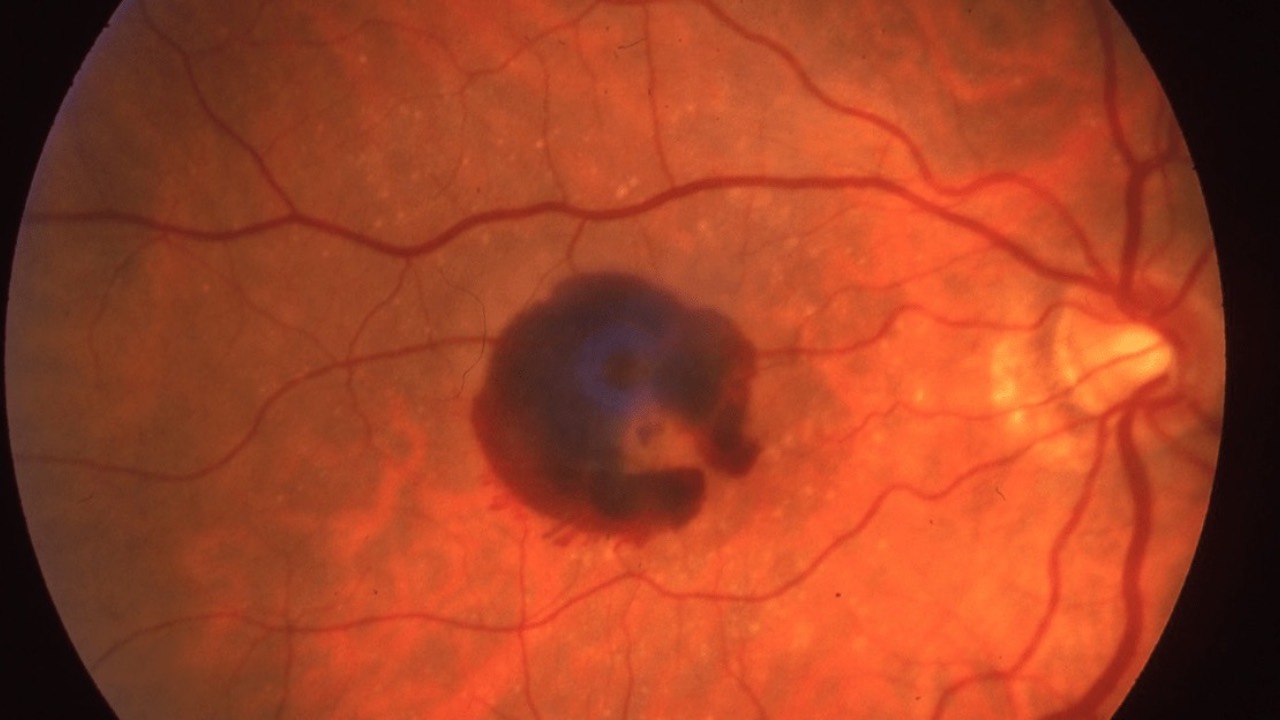

Hair Dye Retinopathy

Retinopathy associated with hair dye aromatic amines (RAHDAA) may be an emerging concern. This condition manifests as multiple bilateral serous retinal detachments, mimicking MEK inhibitor-associated retinopathy.

Symptoms are typically following exposure to hair dyes containing aromatic amines. ...